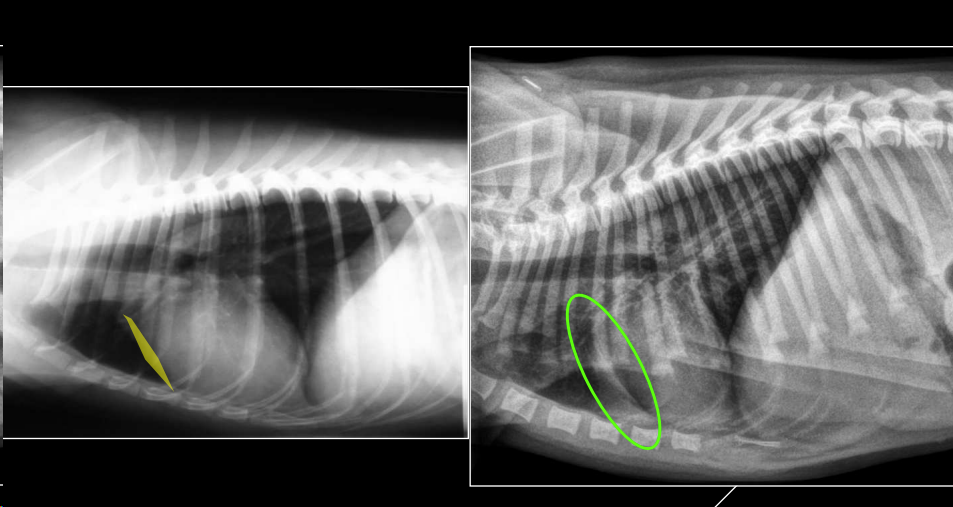

- Divergencia 10–20° con raquis torácico.

Alteraciones detectables:

- Desplazamientos (dorsal o ventral).

- Dorsal: cardiomegalia, masa craneoventral.

- Ventral: dilatación esofágica, masa craneodorsal.